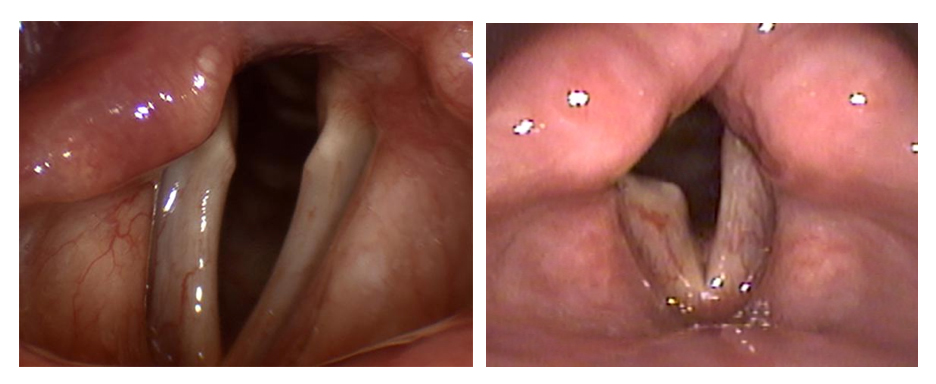

Наличие слабости или паралича голосовых связок может быть продемонстрировано с помощью эндоскопического обследования гортани, которое ЛОР врач проводит после тщательного опроса истории болезни пациента. К обследованию можно добавить измерения звука и электромиографию (ЭМГ) мышц голосовых связок. Информацию о том, как будет проходить процесс восстановления нервных функций, можно получить с помощью ЭМГ. Учитывая возможные причины паралича голосовых связок, пациенту могут быть выполнены компьютерная томография шеи и легких и / или магнитно-резонансная томография (МРТ) головного мозга.